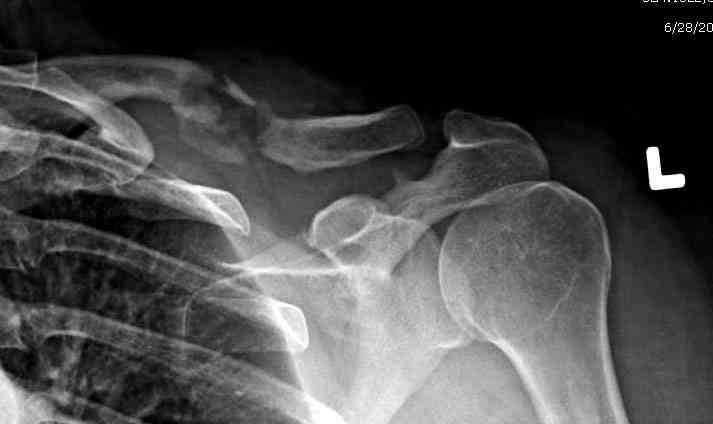

ГГШ> Результат стационарного лечения приведен на рентгенограмме (Xray_3).

Это картинка то есть через неделю после травмы, при выписке? Более чем приемлемо.

после изучения рентгенограмм могу сказать следующее:

1) после репозиции стало хуже

2) стояние фрагментов при выписке идентично таковому при пступлении - с выраженным смещением

Распределение мнений по перечисленным выше категориям приведено на гистограмме (см. Рисунок 1). Мнения разделись, и в аудитории преобладает убеждение, что сохранение смещения ключи.цы на величину диаметра без кортикального контакта между отломками и смещением до 3 см по длине у подростка 15 лет допустимо.

Оценка положения костных фрагментов должна осуществляться по рентгенограммам, вы.полненным в двух проекциях. Стандартная ( и почему.то считающейся достаточной в большинстве наших лечебных учреждений) передне.задняя проекция дополняется шейной проекций под уг.лом 45°. Смещения: расхождение в поперечном направлении, отсутствие кортикального контакта, укорочение ключицы более 1,5 см . недопустимы и должны быть устранены (11,12).

Рисунок 1 Распределение мнений травматологов по вопросу о допустимости сохранения смещения ключицы на величину диаметра без кортикального контакта между отломками и смещением до 3 см по длине (См. определение категорий в тексте)